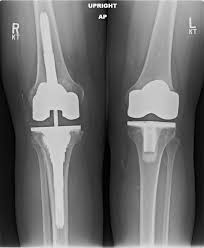

The company ORTHOPEDIC NIKIFOROV was founded in 1998 by the candidate of medical sciences. doctor of orthopedic-traumatologist of the highest category Nikiforov IA Owing to high professionalism and results of work, ORTONIC has gained well-deserved reputation and reputation among colleagues and population of Dnepropetrovsk region and CIS countries (Russia, Moldova, Armenia, etc.). The principle of the enterprise is NO IMPOSSIBLE, it is based on knowledge, experience and active implementation of modern technologies in orthopedics and traumatology. Conservative methods of treatment include individual selection of medicines, therapeutic blockades, manual therapy, massage, physiotherapy (vibration table, magnetotherapy, bioptron, electromyostimulation, etc.), rehabilitation with the suggestion of the necessary concomitant devices and means for the fastest recovery (corsets, bandages, various joint fixators, crutches, walking sticks, etc.). Various minor invasive interventions (chymonucleolysis, vertebroplasty, kyphoplasty, percutaneous nucleoplasty using cold plasma) that are performed on an outpatient basis are successfully used to treat problems associated with spine pathology. The latest modern treatment methods introduced in our company are endoscopic operations using the TYSSES technique of Joimax (Germany) with intervertebral hernias, stenosis and other pathologies of the spine, which allow to avoid complications occurring during open operations and the accompanying general anesthesia. We have many years of successful experience in traditional and modern minimally invasive endoprosthetics of large and small joints, which remains the main direction of our activity. Our company is the exclusive representative of the German company IO International Orthopaedics Holding GmbH, which based on the already known prostheses, its ideas and technological capabilities, has developed and implemented a new concept in hip replacement - an artificial joint prosthesis (ICON). We assist interested colleagues in training the operative technique for installing an artificial joint prosthesis - ICON, both in the workplace and in Germany. For 20 years we have been successfully cooperating with Sanitatshaus Gerd Klinz ortho team, an enterprise that for 20 years has been one of the leading places in Germany for the production of functional prostheses of the upper and lower limbs, as well as cosmetic prostheses of limbs and other body parts (nose, ears, eyeballs, fingers). We have an atmosphere of friendliness and human participation. Politeness, benevolence, the desire to understand and help is the basis of our attitude towards patients. We are always glad to see you and will do our best to make you feel great! We are waiting for you at: Ukraine, Dnepr, Gagarin Ave., 13 (under reconstruction) on all questions to address: tel .: +38 (050) 488-88-92 E-mail: orthonik.ukr@gmail.com Germany, Spine Nano Klinik, Zeppelinstr. 21, Potsdam Tel. +4901801121919 E-mail: kmw.nikiforov@hotmail.de